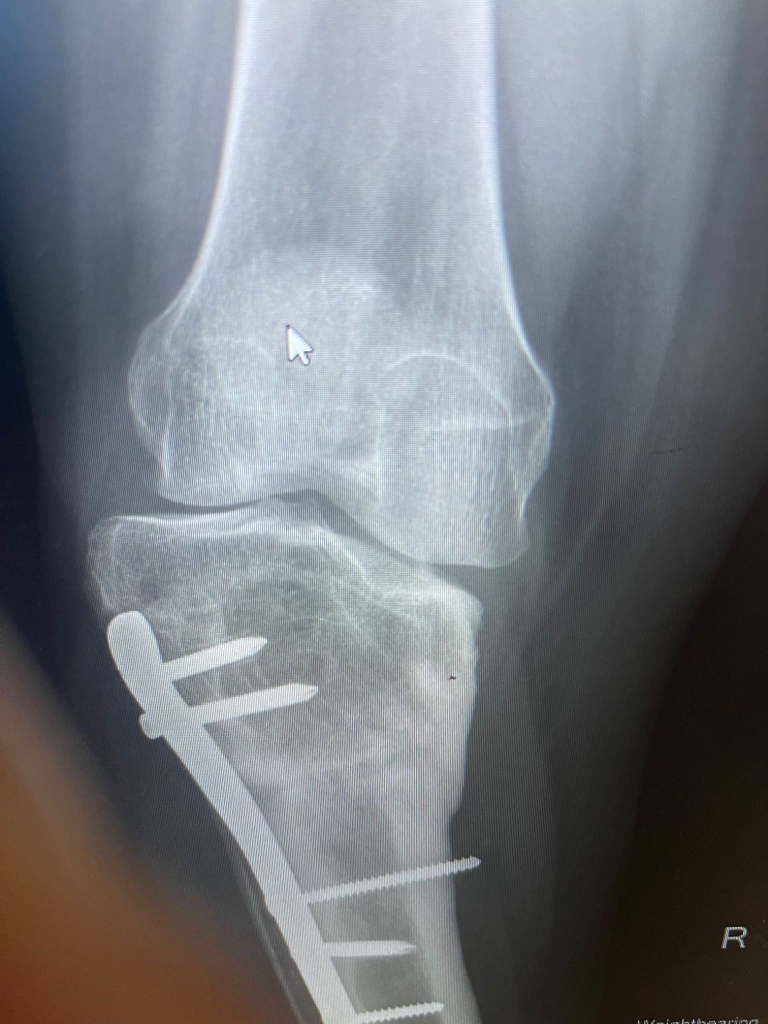

Tibial osteotomy - (5-50)

Removal of internal fixation from bone / joint, excluding K-wires +/- image guidance - (1-5)